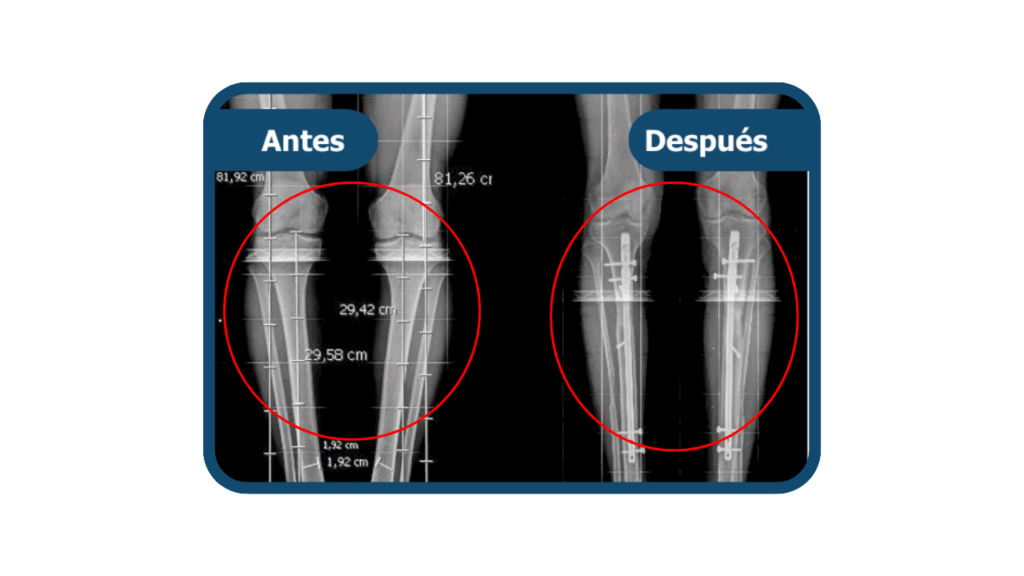

Dismetría ósea

Es una condición en la que existe una diferencia de longitud entre una pierna y la otra, lo que puede generar alteraciones al caminar, dolor lumbar y sobrecarga articular. En Clínica Arthrosalud es común llevar casos de dismetría ósea.

Para la corrección de casos moderados o severos, se realiza la cirugía de alargamiento óseo, que permite igualar la longitud de las extremidades y restaurar la alineación corporal.